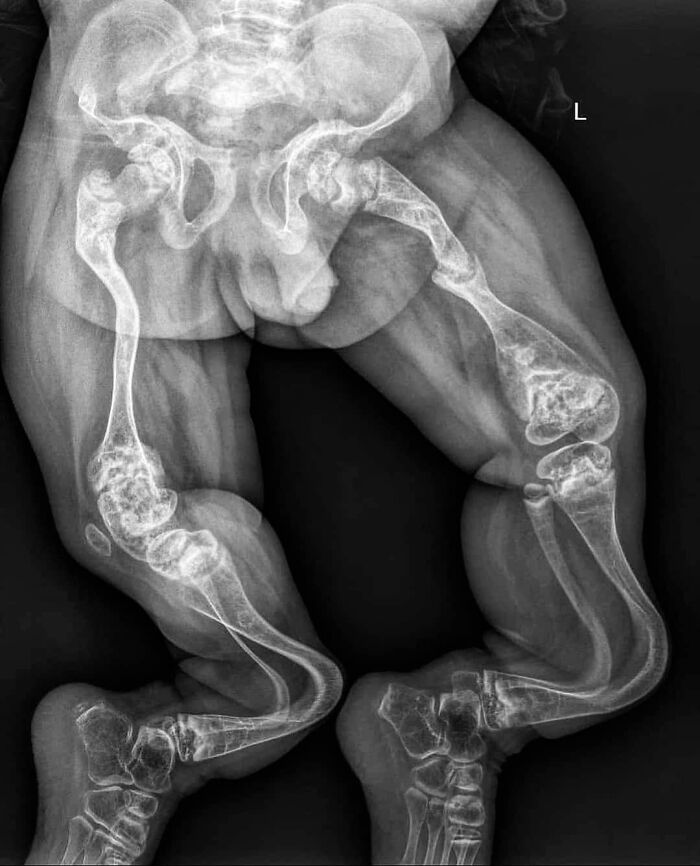

Radiografía de un niño con osteogénesis imperfecta tipo III, con deformidades progresivas en las extremidades inferiores, osteoporosis grave, huesos frágiles y coxa vara.